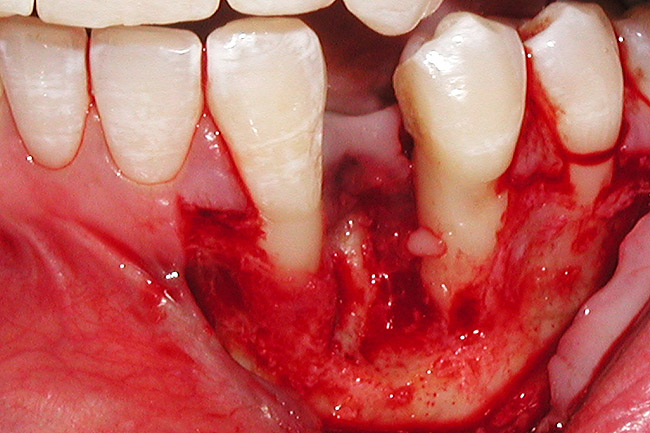

Figure 4  Vertical ridge defect in site No. 22.

Figure 4

Figure 5  Horizontal ridge defect in site No. 22.

Figure 5